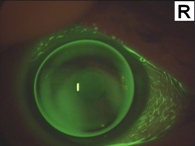

Bei der optischen Korrektion ist die Kontaktlinse der Brille weit überlegen, weil die Unregelmäßigkeiten der Hornhaut durch die Tränenflüssigkeit hinter der Linse ausgeglichen werden. Ist der Keratokonus so weit fortgeschritten, dass wegen zentraler Vernarbungen oder zu ungünstiger optischer Verhältnisse keine sinnvolle Kontaktlinsenkorrektion mehr möglich ist, sollte eine Hornhauttransplantation (Keratoplastik) in Betracht gezogen werden. Auch, wenn in einigen Fällen nach der Operation noch immer keine gute Brillenkorrektion möglich sein sollte, ist mit einer Kontaktlinse meist wieder eine Sehschärfe von 80% bis 100% zu erzielen.